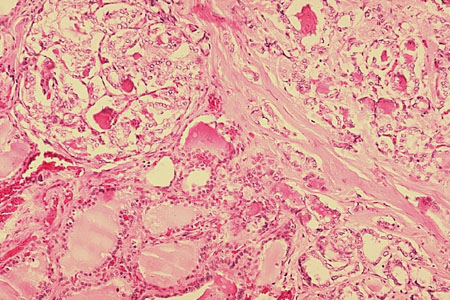

[Figure caption and citation for the preceding image starts]: Histopatologia de carcinoma folicular, tireoideCDC Image Library/Dr Edwin P. Ewing, Jr [Citation ends].

No entanto, para neoplasias foliculares ou oncocíticas, a citologia não diferencia entre adenoma (benigno) e carcinoma.[47]Ahn HS, Kim HS, Hong MJ. Ultrasonographic and cytologic assessments of follicular neoplasms of the thyroid: predictive features differentiating follicular carcinoma from follicular adenoma. PLoS One. 2022 Jul 21;17(7):e0271437.

Nesses casos, a testagem molecular ou cirurgia (por exemplo, lobectomia) para observar a presença de invasão capsular ou vascular são necessárias para confirmar o diagnóstico.[29]Gharib H, Papini E, Garber JR, et al. American Association of Clinical Endocrinologists, American College of Endocrinology, and Associazione Medici Endocrinologi medical guidelines for clinical practice for the diagnosis and management of thyroid nodules - 2016 update. Endocr Pract. 2016 May;22(5):622-39.